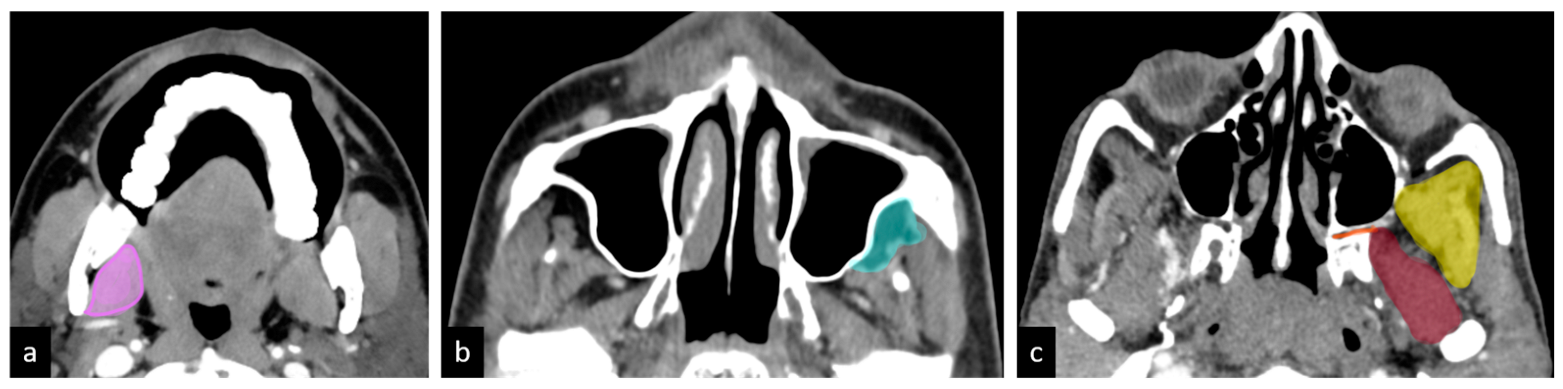

- Compartment 1: Low ITF (medial pterygoid)

- Compartment 2: Anterior high ITF (retroantral fat)

- Compartment 3: Posterior high ITF

- Compartment 3a: Paramandibular compartment (paramandibular fat/temporalis)

- Compartment 3b: Muscle compartment (lateral pterygoid)

- Compartment 3c: Perineural compartment (PPF/PMF).

- Compartment 1: Loss of fat planes with medial pterygoid.

- Compartment 2: Tumor extension into the high retroantral space, manifesting as mass or fat stranding.

- Compartment 3a: Loss of fat planes with temporalis muscle above the sigmoid notch or increased temporalis bulk with associated paramandibular soft tissue involvement.

- Compartment 3b: Loss of fat planes with lateral pterygoid muscle.

- Compartment 3c: Tumor extension into the pterygomaxillary fissure or pterygopalatine fossa.